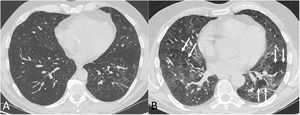

Four thoracic radiologists from Hospital Universitario Ramón y Cajal (AUV, JJMP, LGS and JJAR) reviewed the chest CT findings for 59 patients with a history of SARS-CoV-2 pneumonia with persistent respiratory symptoms, fibrotic-like lesions on chest X-ray and/or abnormal PFT results. The chest CT scans were performed within a maximum period of three months from hospital discharge, with a high-resolution volumetric technique (1mm slices), without intravenous contrast, and including an expiratory phase. The results are shown in Table 1, where we see a clear predominance of males (73%) over females (27%), reflecting the demonstrated greater severity of pneumonia in males. The most common CT findings were bronchial dilation (80%, primarily peripheral) and parenchymal bands (78%), consisting of elongated opacities 1−3mm thick in the lung parenchyma, subpleural in location or extending up to the pleural surface, frequently with distortion of the lung architecture (Fig. 3). Other findings identified in more than half of the cases were: 1) coarse subpleural reticulation with irregular interfaces due to architectural distortion, but with no honeycombing, which we have called subpleural interstitial involvement without honeycombing (66%); 2) areas of ground-glass opacity (58%) (Fig. 4); and 3) a mosaic pattern due to air trapping demonstrated in the expiratory phase of the scan (51%) (Fig. 5). In 14% of the patients we demonstrated the existence of pneumatoceles, the development of which is probably related to mechanical ventilation, which 75% of our patients with these lesions had required. The least common finding was honeycombing (4%) (Fig. 6). In practically all patients, the involvement was bilateral (98%) and peripheral (98%), with a predominance of middle (93%) and lower (86%) fields, in line with what has been reported in other articles.17,33,34,37

The most common findings on chest computed tomography (lung parenchyma window) in post-COVID-19 patients with radiological sequelae are subpleural parenchymal bands ("band opacities" and "subpleural lines", long arrows) with distortion of the lung architecture and secondary bronchial dilation (short arrows).